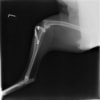

雑種犬 推定10歳 避妊雌

本症例は、走った後に左後肢を挙上していることを主訴に来院されました。触診時に左膝関節のクリック音を聴取、レントゲン検査にて左脛骨の前方変位が認められました。術中に、前十字靱帯の断裂及び内側半月板の損傷、内側の軟部組織の顕著な腫脹を確認。半月板切除、TPLOを実施しました。周囲組織への炎症の波及もあったため回復に時間を要しておりますが、徐々に跛行頻度は減少傾向にあり、現在も経過観察中です。術前に約29°あったTPAは術後に約10°まで矯正されました。

術前写真

術後写真

手術前後のTPA(脛骨高平部の角度)を測定しています。

約29°から約10°へ矯正されています。